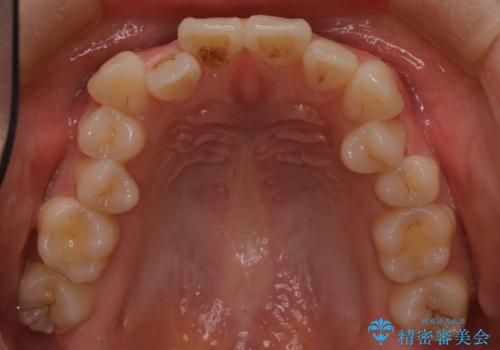

八重歯と前歯の逆の咬み合わせを、目立たない矯正で同時に改善

- 八重歯と、右上前歯(2番)が下の歯より内側に入っている反対咬合を気にされてご来院されました。精密な検査の結果、八重歯と反対咬合を同時に改善するためには、歯列全体にスペースを確保する必要があると判明。患者様のご希望から、透明で目立たないインビザライン(マウスピース矯正)による治療計画を立案しました。奥歯全体を奥へ動かす遠心移動でスペースを作り、これらの複雑な問題を一括で解消することを目指します。

今回の矯正治療では、透明なマウスピース型の装置インビザラインを使用しました。治療は、緻密なデジタル計画に基づき、奥歯から順に歯列全体を後方へ移動させる遠心移動を実施。これにより、八重歯を正しい位置に並べるためのスペースを確保しました。同時に、右上の2番を前方に誘導することで反対咬合を解消。結果として、抜歯することなく八重歯と反対咬合という複数の問題が改善され、機能的で美しい歯並びを獲得していただけました。